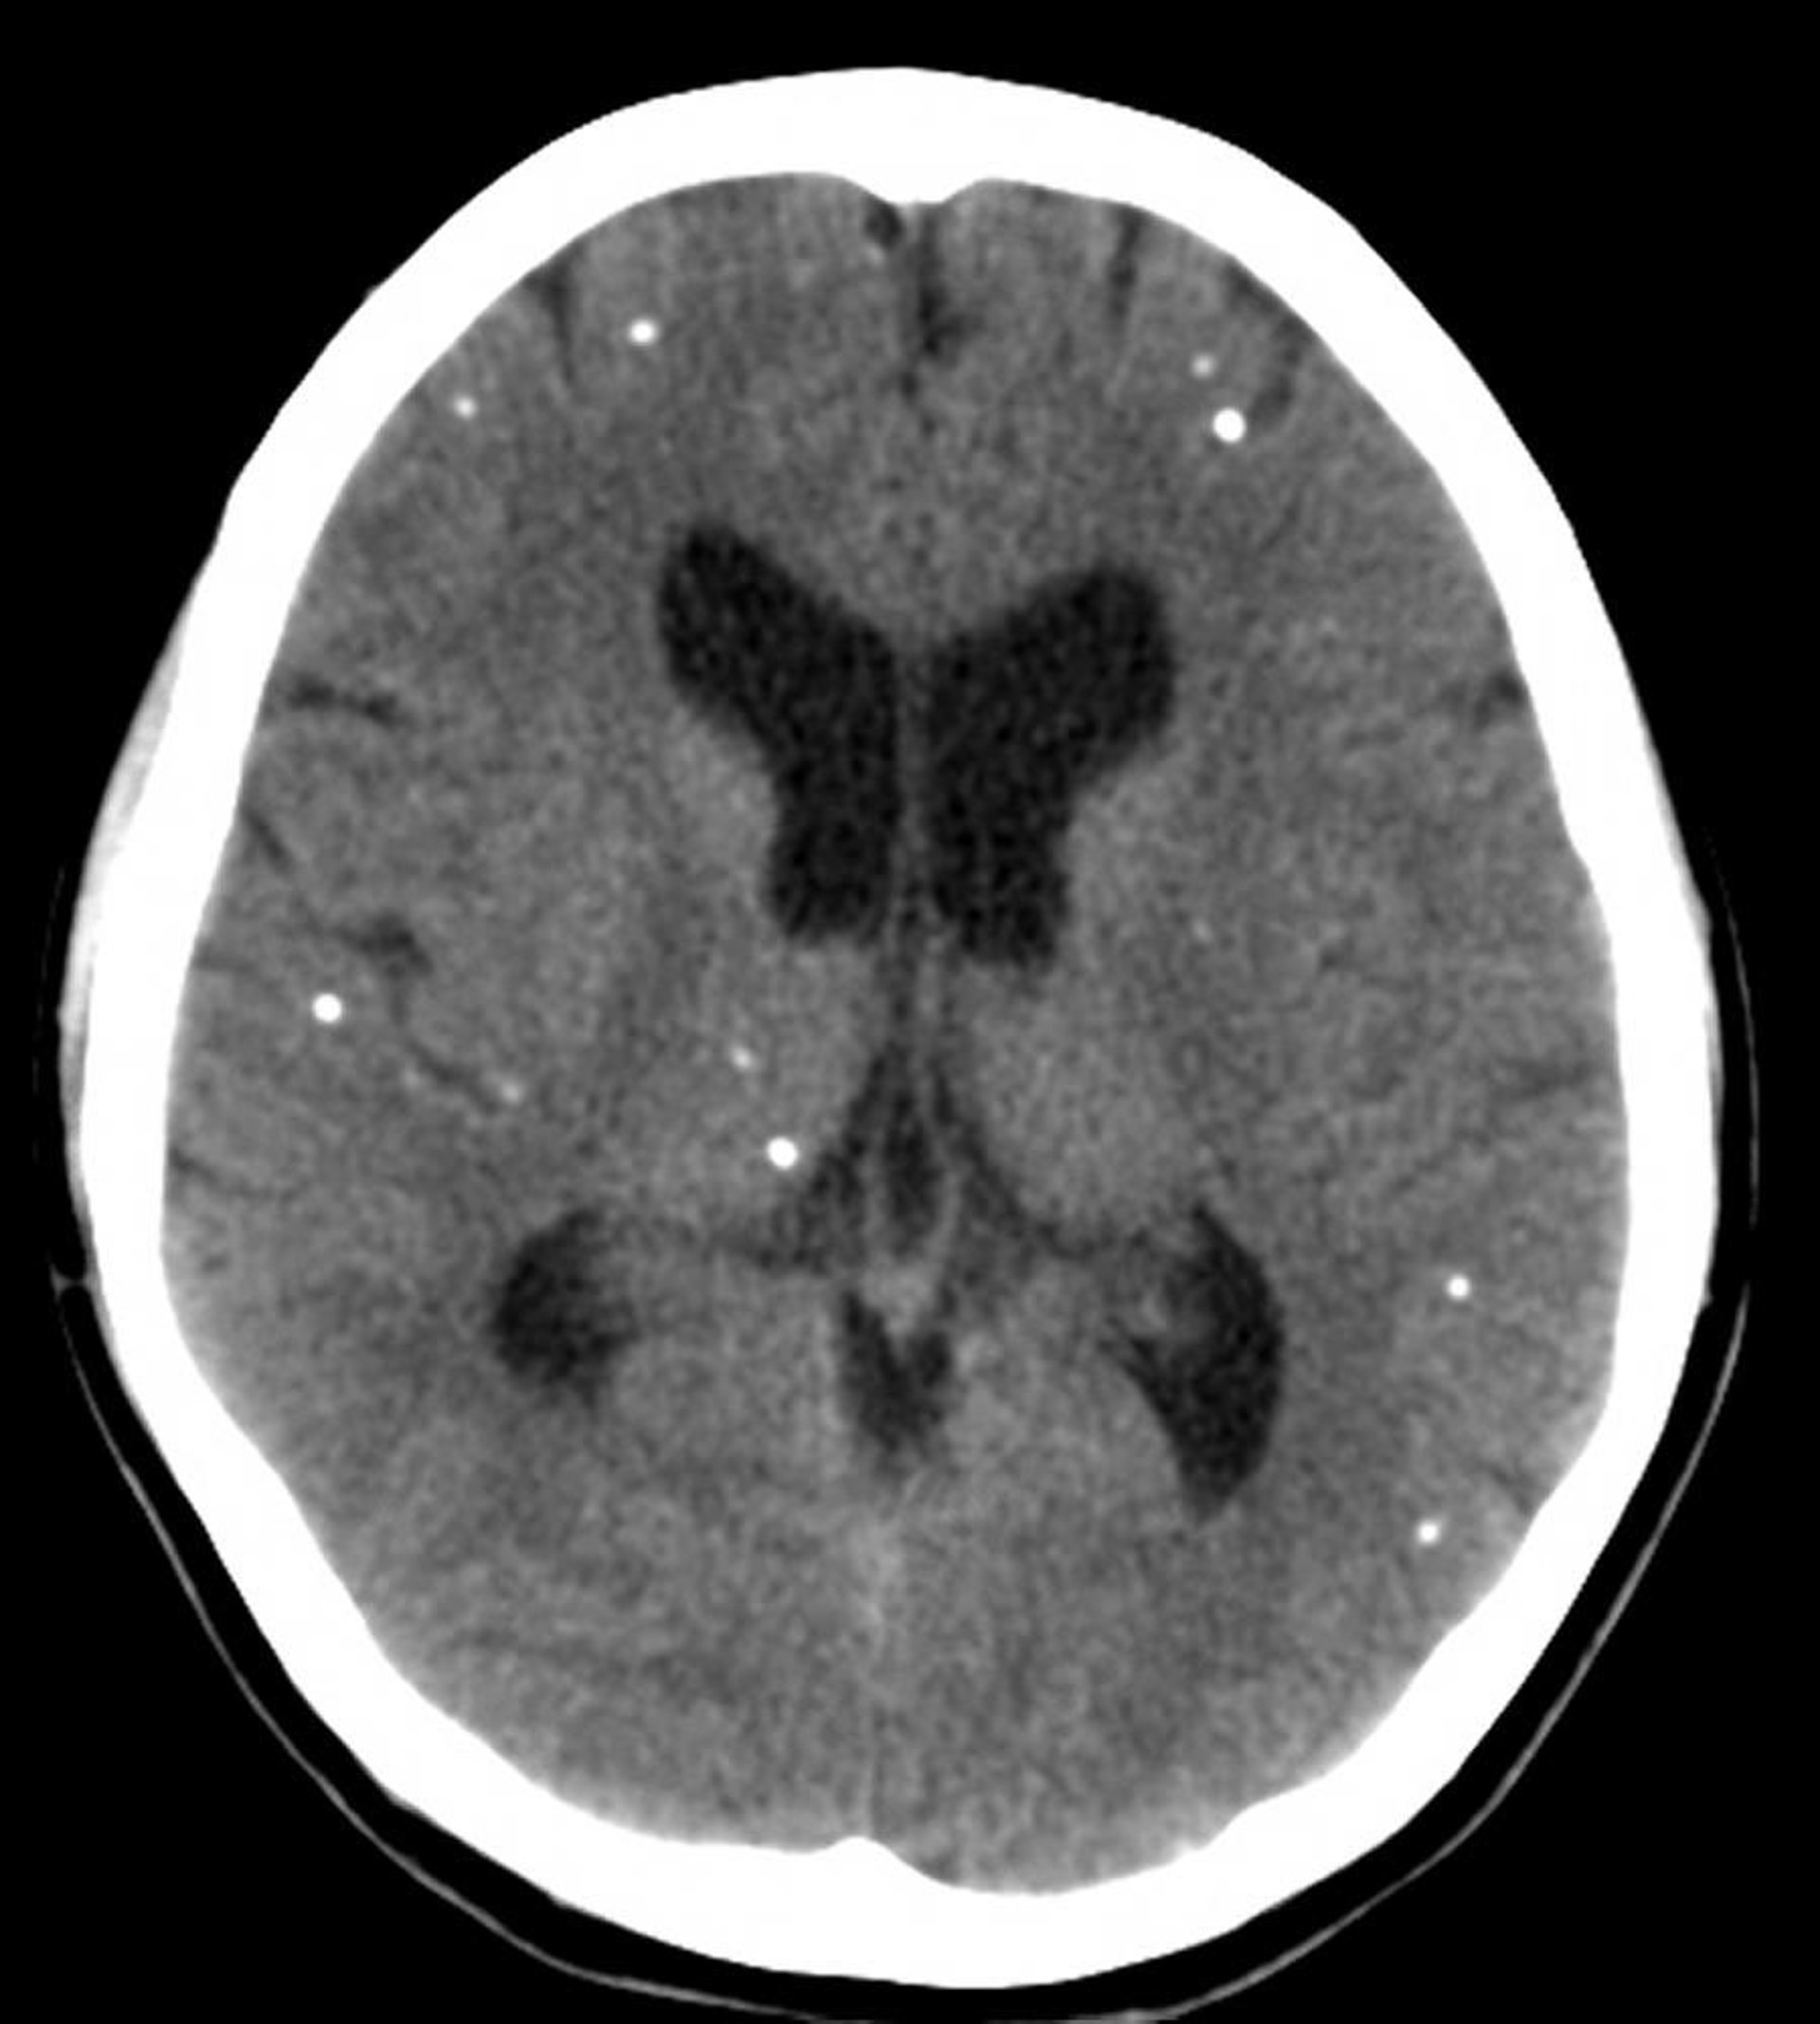

Neurocysticercose

Cette TDM montre des calcifications multifocales représentant des kystes calcifiés chez un patient atteint de neurocysticercose.

Courtesy of John E. Greenlee, MD.